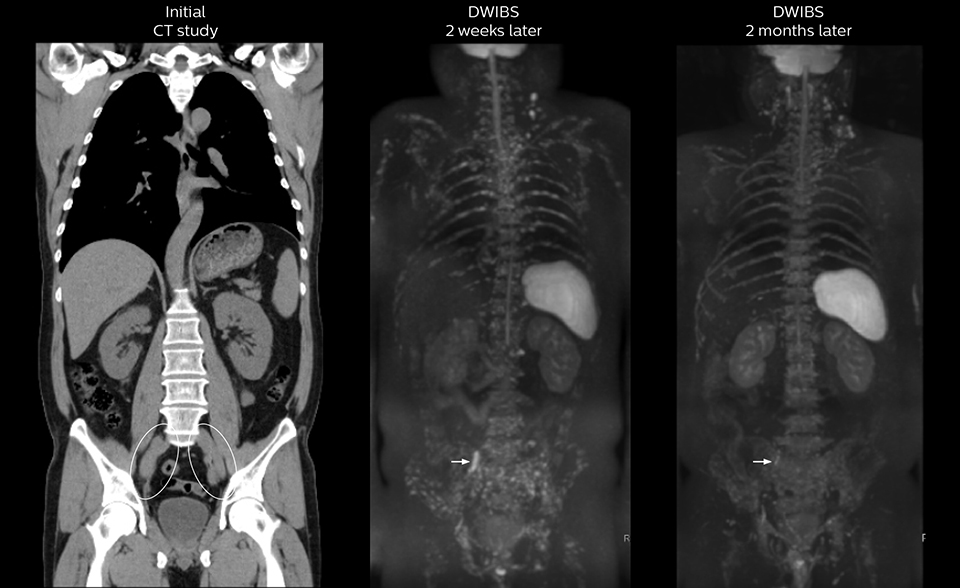

“The DWIBS sequence’s value in oncology cases is due to the high contrast it creates between lesions and surrounding tissue. Whole body DWI is requested by physicians who need to clarify TNM staging or determine therapeutic strategies, oncologists in need of diagnosis or follow-up scans, surgeons who need to see the presence of distant lesions that are sometimes difficult to detect by CT before surgery, and urologists for the evaluation of bone lesions, and the effect of chemotherapy and radiotherapy.”

After implementing the improved whole body protocol, the radiology team initially did not see a large increase in referrals, although Dr. Nobusawa saw clinical cases where the DWIBS images provided him valuable information for diagnosis. This is why Dr. Nobusawa and Mr. Naka started to actively educate referring physicians about the value of whole body DWIBS. They organized several presentations for physicians in the hospital, where they explained how DWIBS can be of value in oncology patients. The information it provides can be useful for physicians when staging cancer, as well as when determining or adjusting treatment strategy. Mr. Naka remembers some cases where DWIBS provided remarkable information. “In one example, DWIBS visualized bone lesions that could not be seen on PET or SPECT. In another case we had found a bone lesion when a normal L-spine scan for narrowing of the disk space was done. One extra DWIBS scan (2 stations, 8 minutes) demonstrated a lesion that later was confirmed to be the primary region of cancer.”

In certain cases, radiologists now choose DWIBS to make diagnoses that used to depend on nuclear medicine studies. “We don’t have SPECT or PET in our hospital, so for instance for visualizing metastasis and monitoring the effect of treatments such as chemotherapy or radiotherapy, we used to refer patients outside the hospital. Now, these patients are sent to MRI for our whole body protocol with DWIBS,” Mr. Naka says.